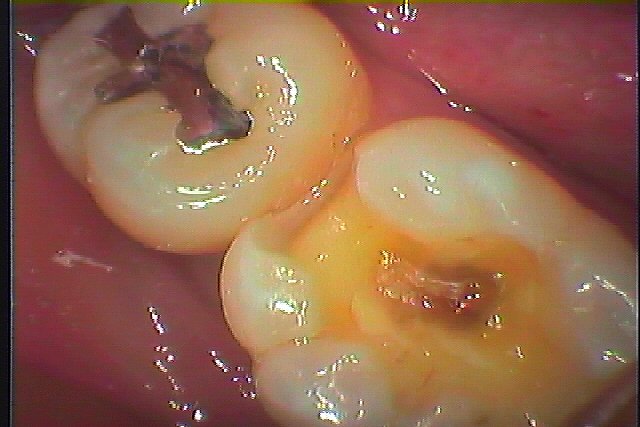

下顎の6番 見えるところの銀歯は外してセラミックへやり変えていきたい|お知らせ |広島市安佐南区の歯科医院 下顎の6番 見えるところの銀歯は外してセラミックへやり変えていきたい トップ お知らせ・ブログ お知らせ 下顎の6番 見えるところの銀歯は外してセラミックへやり変えていきたい 下顎の6番 見えるところの銀歯は外してセラミックへやり変えていきたい この銀歯をはずしていきます 外すとこんな感じになっていました 下には虫歯が存在していました 遠心部も虫歯で伸ばしました 7番は大丈夫でした 近心部も虫歯で伸ばしました 5番の方まで虫歯になっていました 虫歯を除去しCR樹脂にて修復しています 6番はCR樹脂にて覆罩を行っています セレックセラミックが綺麗に入りました 喜んでいただきました Web診療予約 初めての方へ 選ばれ続ける理由 院内設備について 歯が痛いしみる一般歯科 歯がぐらぐらする歯周病 健康な歯を保ちたい予防歯科 子供の虫歯予防をしたい小児歯科 銀歯をセラミックに審美歯科 白い歯を目指しませんか?ホワイトニング 矯正専門医がいるので安心矯正歯科 抜けた歯を補いたいインプラント・入れ歯 医院案内 スタッフ紹介 メリィハウス歯科クリニックオフィシャルホームページ ラベンダー歯科クリニックオフィシャルホームページ お知らせ・ブログ ホーム 診療科目 一般歯科 歯周病治療 予防治療 小児歯科 審美治療 ホワイトニング 矯正歯科 入れ歯・インプラント マウスピース矯正 初めての方へ 院長・スタッフ 設備紹介 医院案内・アクセス メニューを閉じる